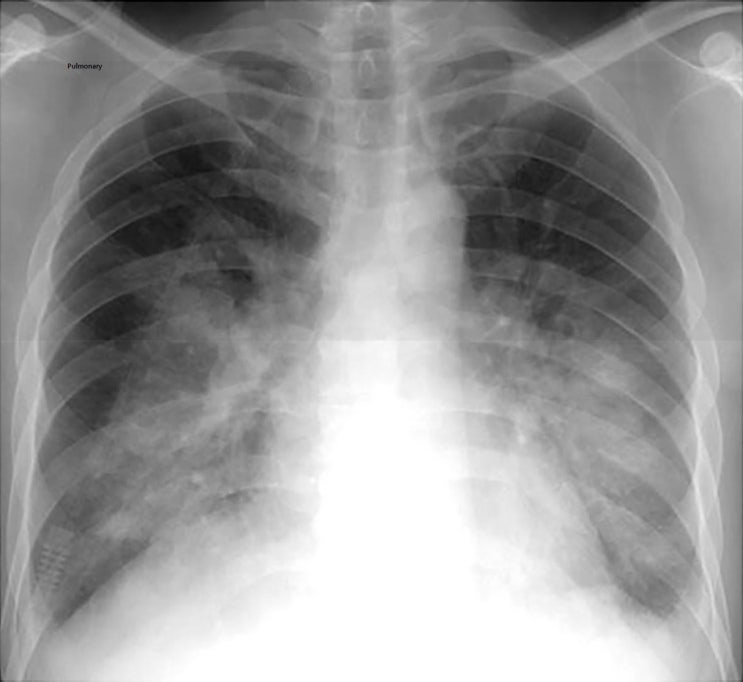

Pulmonary 가능여부 도움받기!!

폐 질환은 매우 중요한 건강 문제이라고해요 만약 폐에 관련된 어떤 가능성이 있다면, 그것을 확인하고 도...